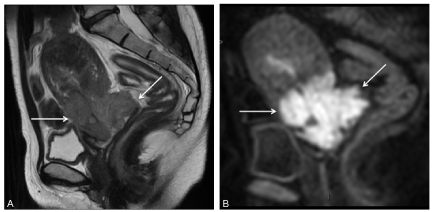

La tumeur apparaît comme une masse cervicale en signal intermédiaire en T2 (figure 21.1A), avec une restriction du coefficient apparent de diffusion (figure 21.1B) et une prise de contraste précoce (30 secondes) en IRM de perfusion.

Fig. 21.1 Coupes IRM en incidence sagittale pondérée en T2 (A) retrouvant une masse tumorale cervicale invasive en signal intermédiaire de taille supérieure à 4 cm et étendue au cul-de-sac vaginal postérieur (flèches), en hypersignal en diffusion (B).

Source : CERF, CNEBMN, 2022.